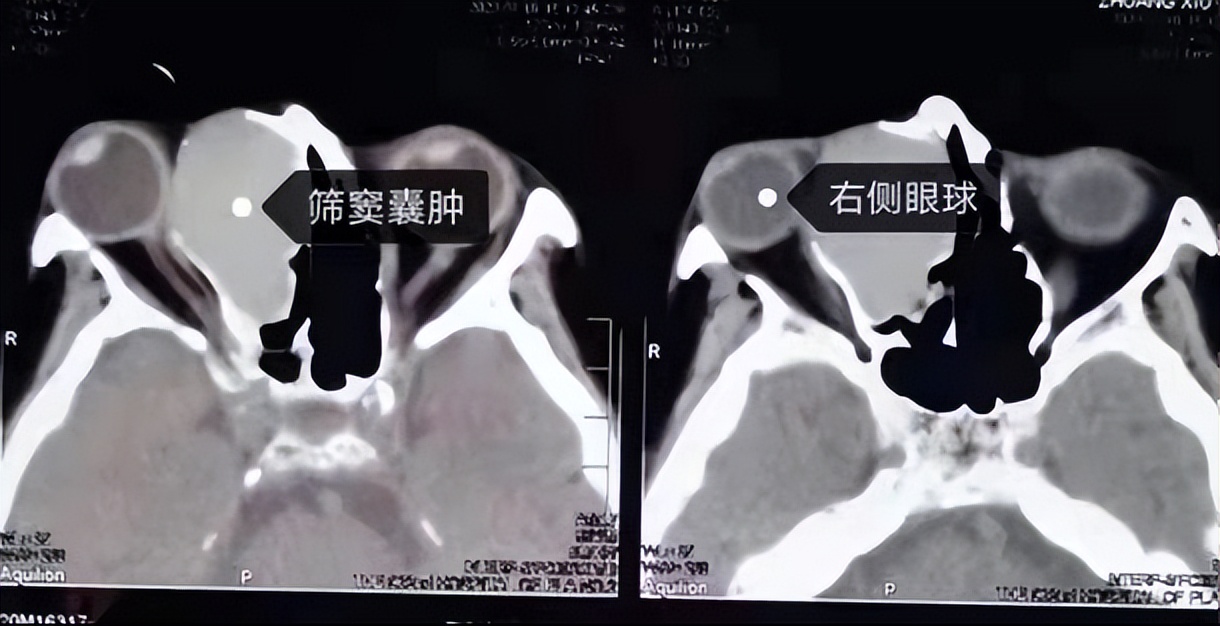

鼻窦黏液囊肿多发生在额窦和筛窦,蝶窦者较少,上颌窦最少,巨大的鼻窦黏液囊肿可侵入眶内和颅内。本病晚期并发感染,可转化为脓囊肿,其破坏性更大,可引起脑膜炎、脑脊液鼻漏或海绵窦血栓等。

鼻窦黏液囊肿的临床表现早期可无任何症状,以后黏液囊肿逐渐增大,压迫囊壁,引起头痛。若突入眶内可使眼球移位,并有复视、流泪、视力障碍等症状。囊肿发生于筛窦者眼球向外移位,发生于额窦者眼球向外下方移位。蝶窦黏液囊肿症状复杂,可致眼球突出,并压迫眶尖而致失明、眼肌麻痹、眼部感觉障碍和疼痛等症状,出现眶尖综合征。囊肿向上发展压迫脑垂体,可引起闭经、性欲减退、尿崩等内分泌失调现象,若压迫颈内动脉可致该动脉发生血栓。若蝶窦黏液囊肿向前壁破溃,黏液排出到鼻腔,以上症状暂时缓解。囊肿除了出现局部症状外还可以出现高热及周身不适等全身症状。